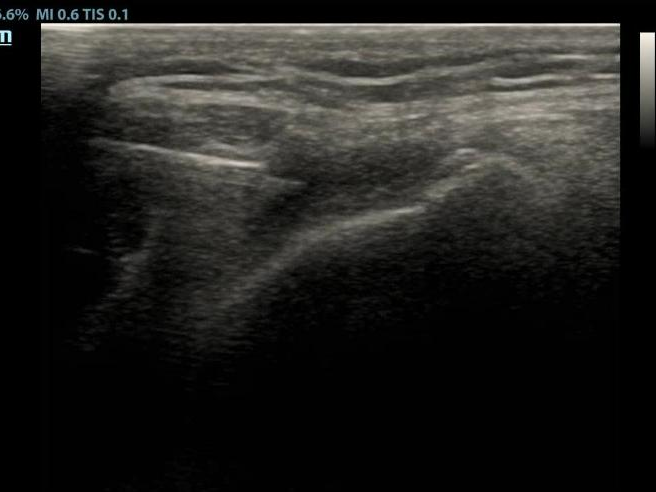

图二:超声引导下穿刺

科室与超声科紧密配合,超声引导下精准操作(图二),关节腔穿刺抽取出淡黄色粘稠液体20ml,病理检查找到尿酸盐结晶(图三)。给予降尿酸、抗炎止痛,辅以中药柴妙饮清热利湿、理气止痛,痛风代茶饮,中药外敷等治疗,患者关节疼痛很快得到缓解,血尿酸水平及炎性指标恢复正常。